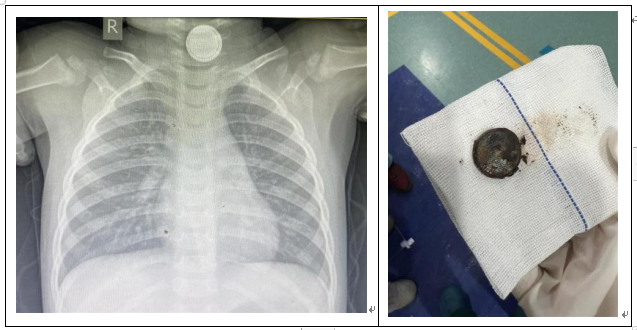

新聞媒體上也不時會報道各地誤吞紐扣電池出現(xiàn)受傷的案例,如2024年4月,湖北一名1歲男童誤吞了一枚紐扣電池,卡在了食道,造成吞咽困難,醫(yī)生經(jīng)手術(shù)從其體內(nèi)取出一塊燒焦的電池,電池的滲出液嚴(yán)重腐蝕了孩子的食道,留下一塊指甲蓋大小的黑痂。(圖2)

圖2 檢查影像和取出的紐扣電池(圖源網(wǎng)絡(luò))